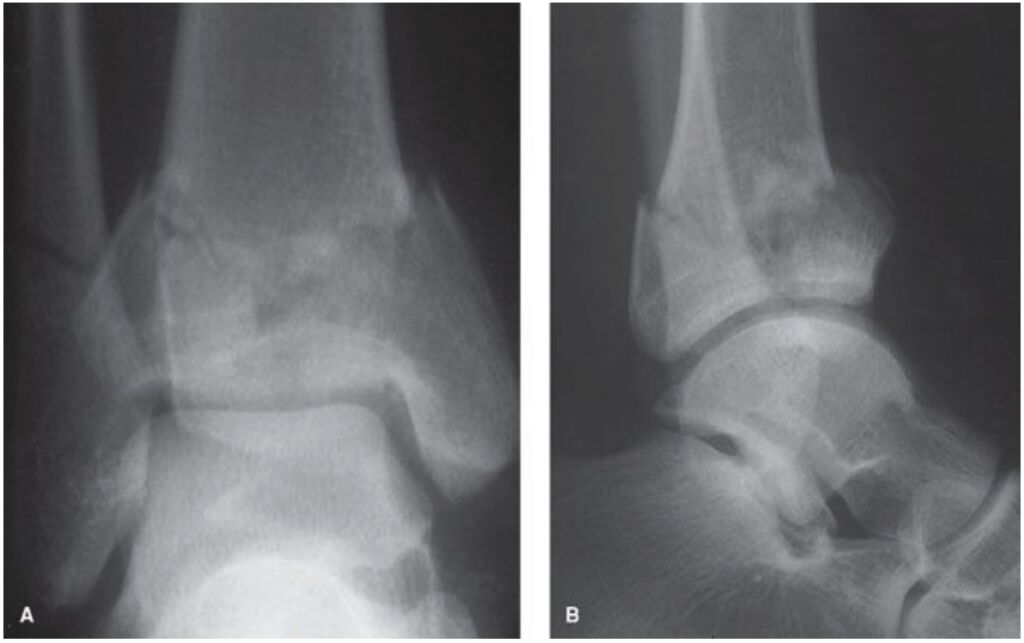

57.55歲貨運工人,工作受傷,右踝疼痛腫脹,下圖為踝部的X光片,其可能之病因、骨折機轉為何?(A)外翻型骨折 (B)垂直壓縮型骨折 (C)內翻型骨折 (D)外旋型骨折